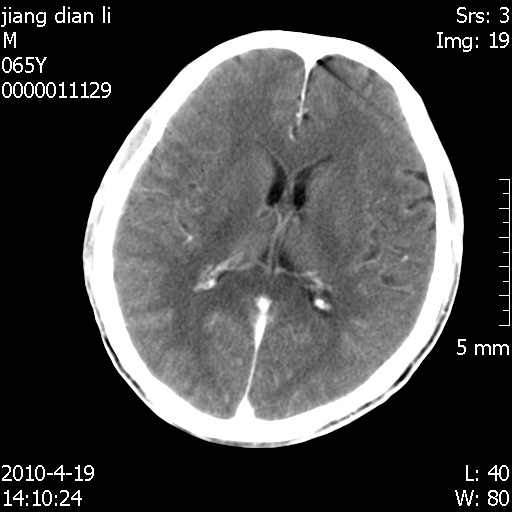

老年男性,突发左下肢无力1天,其余有价值的检查都没有。平扫ct值大约60hu,增强后ct值没什么改变,请大家讨论一下这个病例是什么?说明诊断理由。

左小脑、右大脑顶叶多发圆形高密度病灶,其周环状低密度影。考虑多发脑出血。隔期观察。